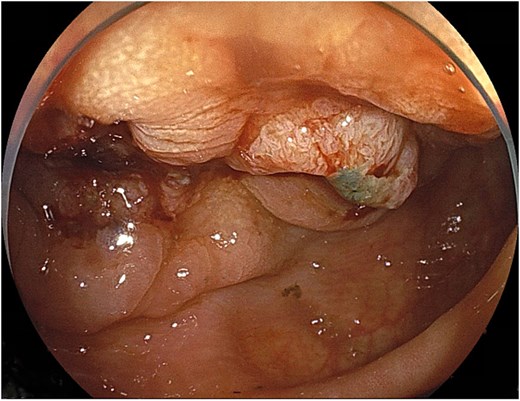

Lower gastrointestinal endoscopy

Endoscopy demonstrated a circumferential type II tumor with severe stenosis in the descending colon (Fig. 1). A self-expandable metallic stent (Boston Scientific HANAROSTENT Naturfit, 22 × 8 cm) was placed to relieve the obstruction.

Circumferential type II tumor with severe stenosis in the descending colon.